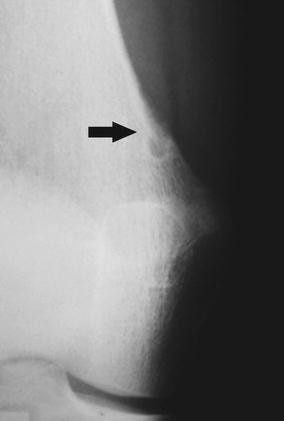

Cortical Desmoid Tumor

Cortical Desmoid Distal Femoral Cortical Irregularity Clinical Mri